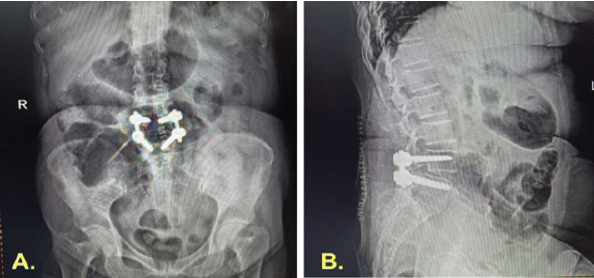

On August 29, 2023, she underwent L4–L5 transpedicular screw-rod fixation, decompression, and posterolateral fusion (Fig. 2). The procedure and early recovery were uneventful. She was mobilized on post-operative day (POD) 2, maintained on strict glycemic control, and discharged on POD 5, ambulating independently with satisfactory pain relief and stable blood glucose levels. The wound was healthy at suture removal on POD 14.

Figure 2: Immediate post-operative imaging following lumbar fusion. Anteroposterior and lateral radiographs showing L4–L5 transpedicular screw-rod fixation with decompression and posterolateral fusion, demonstrating satisfactory implant position.